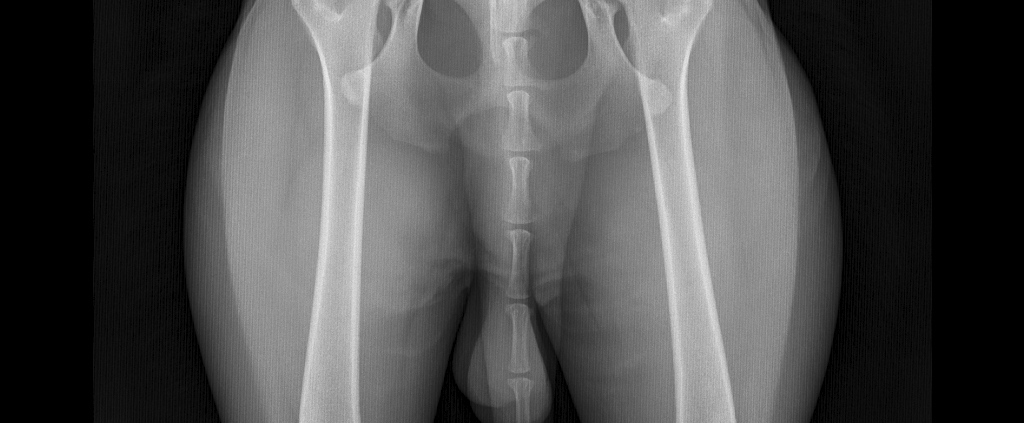

- Digitales Röntgen (HD, OCD, ED): Hochleistungsröntgen mit digitaler Entwicklung